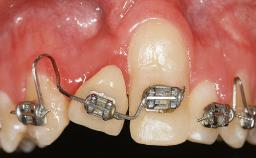

In 1983, a 51-year-old non-smoking patient was referred for the treatment of moderate chronic periodontitis. At the initial examination, 47% of sites exhibited probing depths of 4 to 6 mm. Periodontal therapy consisted of initial periodontal treatment including oral-hygiene instructions and supra- and subgingival debridement, followed by periodontal surgery to eliminate residual pockets.